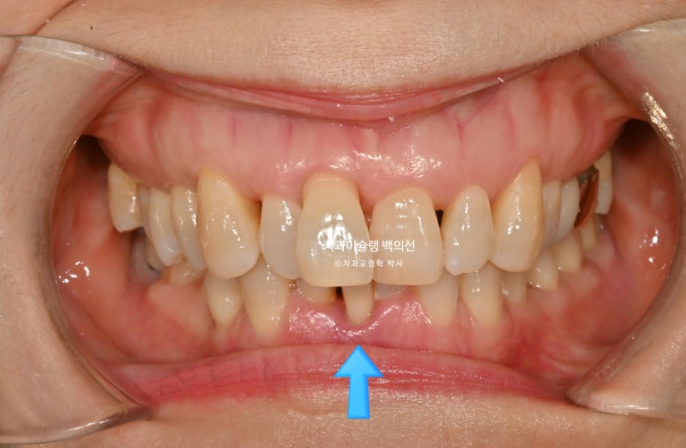

1년 전 치아 틀어짐이 점점 심해지면서 찾아오신 50대 환자분

예전에는 입이 편하게 다물어졌었는데 치아가 틀어지고 벌어지고 내려오면서 이제는 입이 편하게 안 다물어지는 것도 불편한 상태입니다.

파란 화살표 치아는 잇몸이 검붉게 보입니다.

엑스레이상 이미 치주염이 상당히 진행이 되어 발치가 불가피한 상황이였습니다.

위 앞니는 잇몸이 꽉 잡아주지를 못해서 점점 솟아 내려오고 튀어나오면서 치아사이가 벌어졌습니다.

작은어금니도 안으로 쓰러져 있어서 이 부분은 윗니와 엇갈려 물리는 가위교합 입니다.